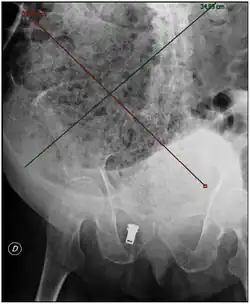

| Plain abdominal X-ray showing a large fecal impaction extending from the pelvis upwards to the left subphrenic space and from the left towards the right flank, measuring over 40 cm in length and 33 cm in width. | |